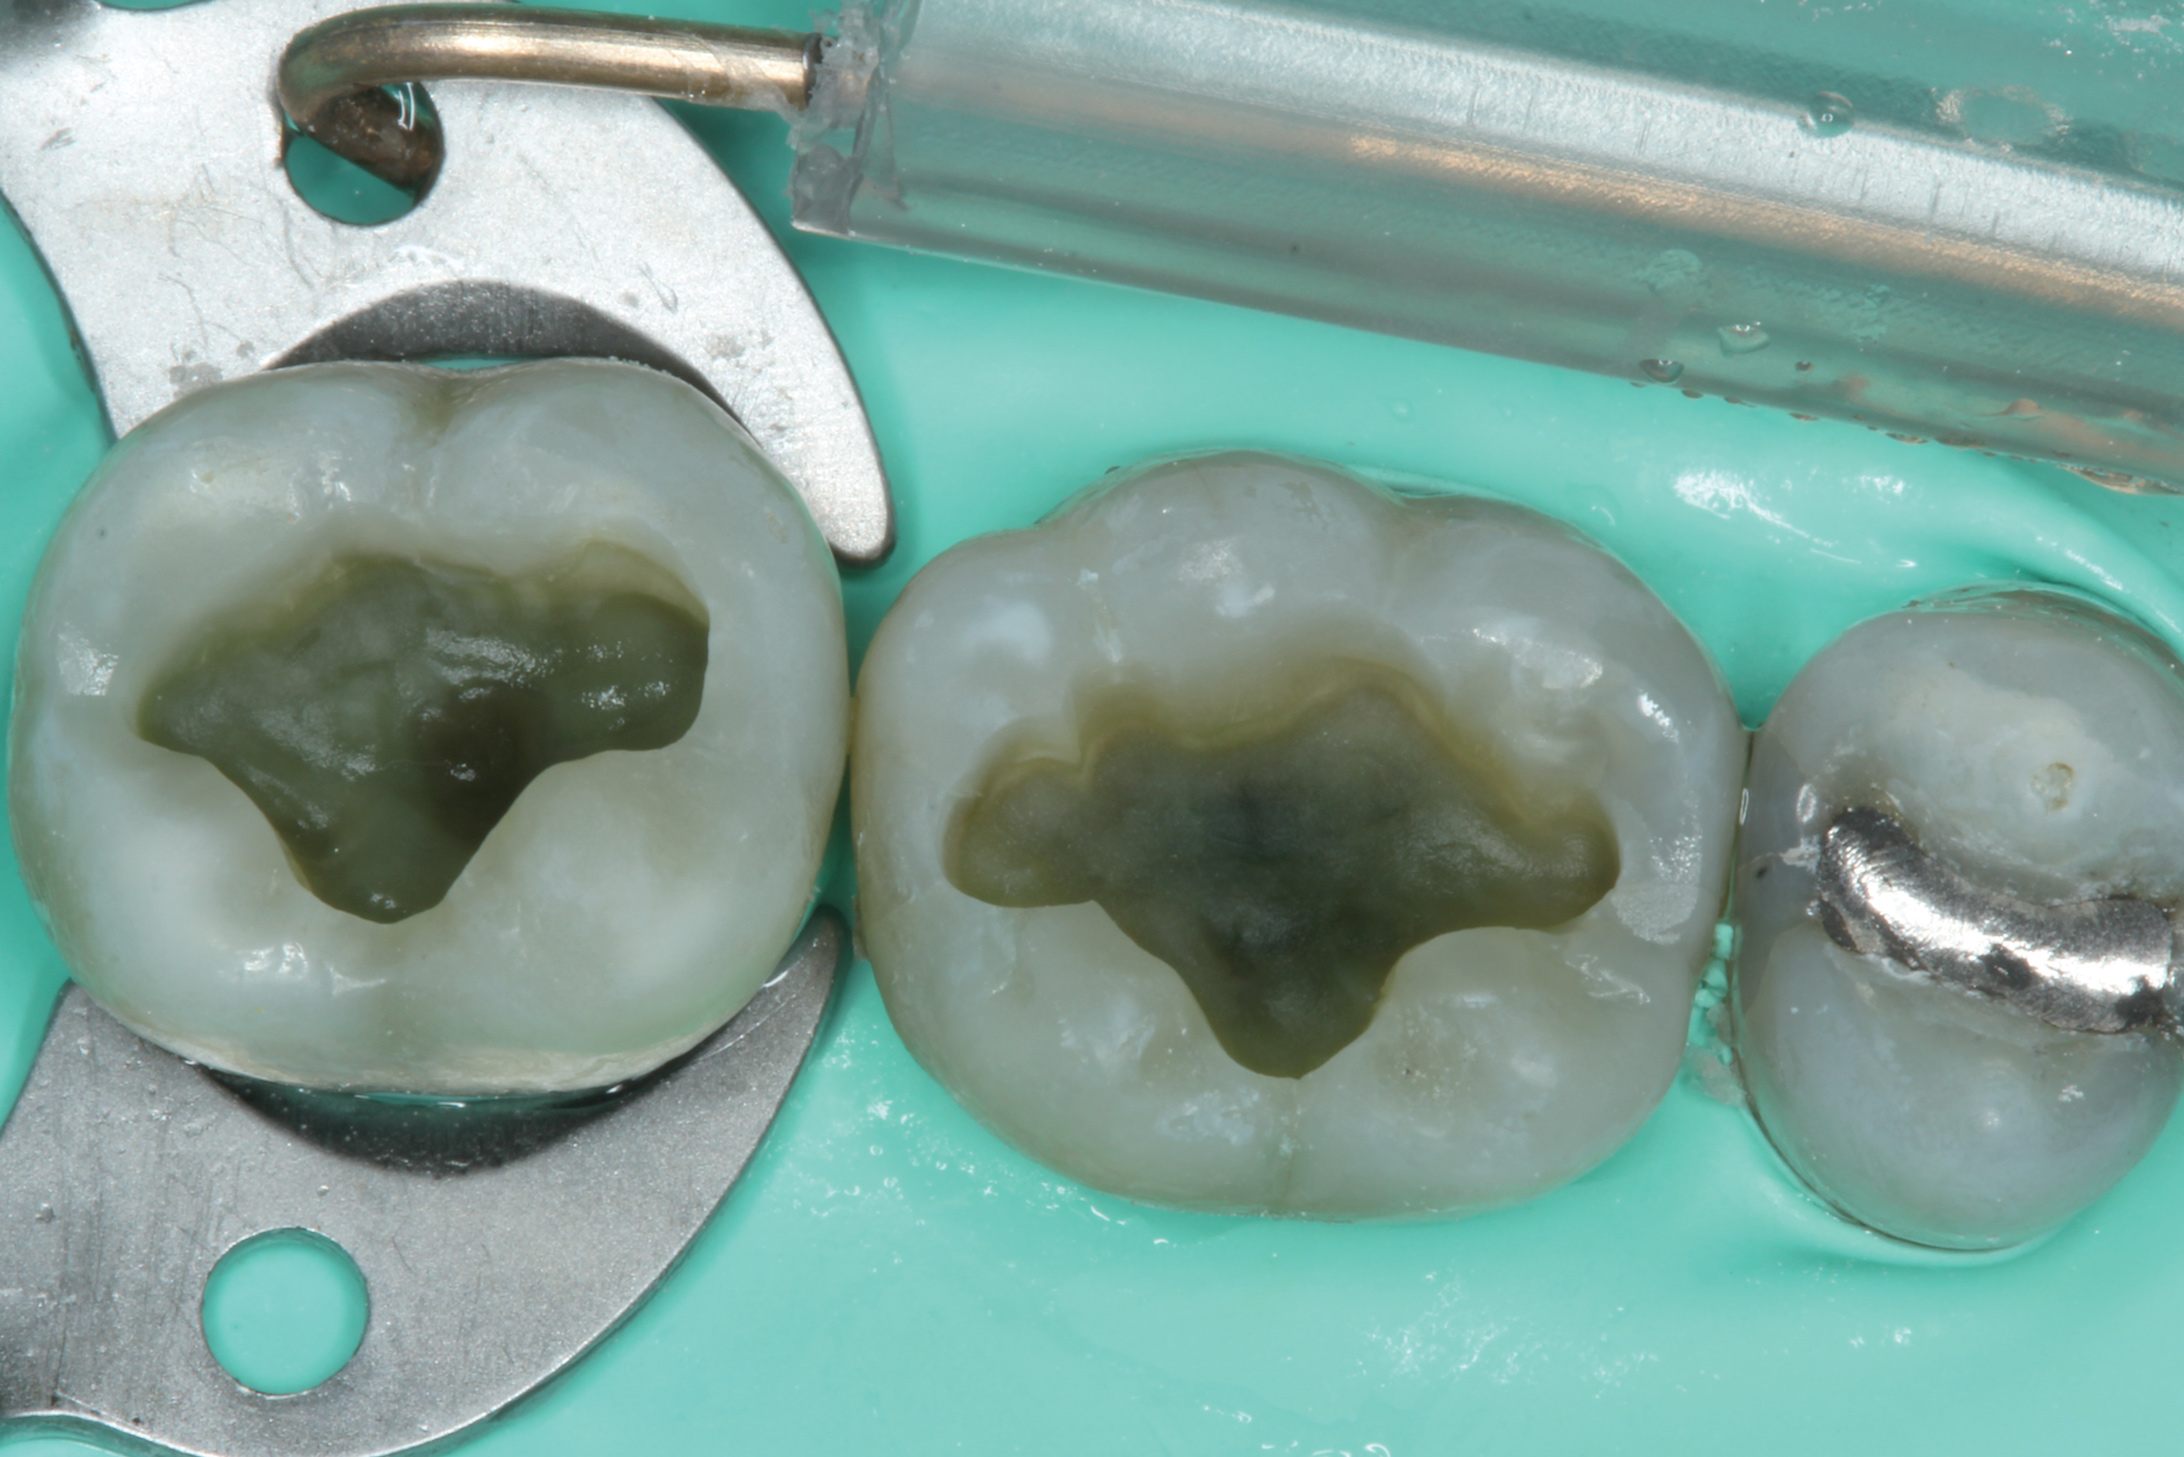

With these limitations acknowledged, visual inspection of tooth preparations after air abrasion reveals that this modality is effective in removing remnant restorative materials, stains, and temporary cement, leaving a clean, matte surface for bonding (Figure 11 through Figure 14). Air abrasion also can smooth the internal aspects of a cavity preparation to help enable better adaptation of the restorative material (Figure 15 and Figure 16). The technique-sensitive nature of adhesive bonding may justify this extra procedure to ensure a clean, smooth preparation.

Fig 13. Crown preparations with temporary cement remnants prior to air abrasion (Fig 13) and after air abrasion (Fig 14) (case by Mohammed Badahman, DDS).

Fig 14. Crown preparations with temporary cement remnants prior to air abrasion (Fig 13) and after air abrasion (Fig 14) (case by Mohammed Badahman, DDS).

Fig 15. Cavity preparation prior to air abrasion (Fig 15) and after air abrasion (Fig 16).